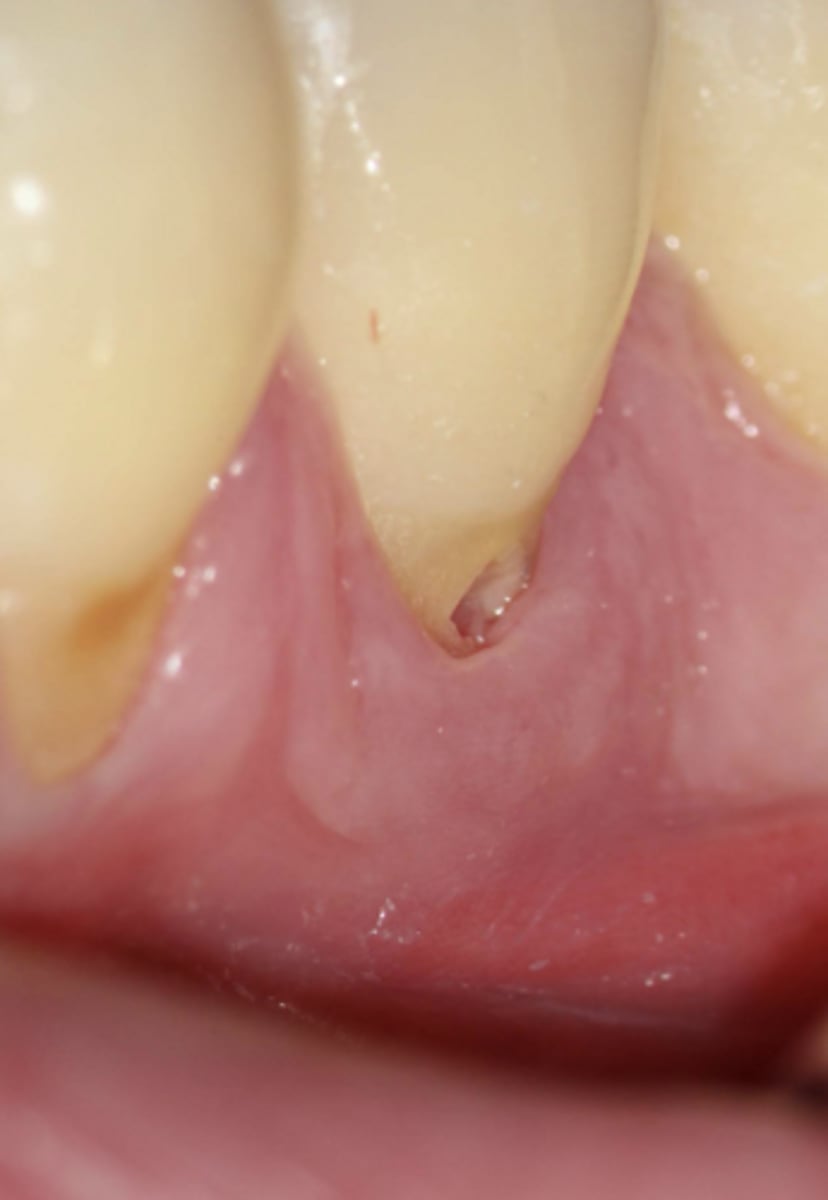

Invasive Cervical Root Resorption (ICRR)

What treatment is indicated?